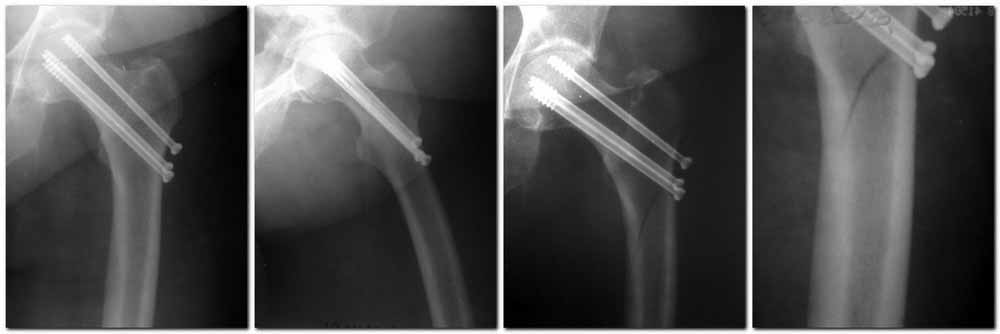

Пациентка Ш. 76 лет, 11 дней назад прооперирована по поводу вколоченного субкапитального перелома шейки левой бедренной кости, 3-мя канюлированными винтами. Вчера пациентка упала в палате. И вот результат- подимплантатный подвертельный перелом левой бедренной кости. Уважаемые коллеги, пожалуйста посоветуйте какой метод дальнейшего лечения предпринять дальше.Соматически пациента повышенного питания, страдает варикозной болезнью нижних конечностей.Из предложенных вариантов коллег - целллокастовая укороченная кокситная повязка, скелетное вытяжение сроком на 40-45 суток - отпали сразу, так как необходимо активизация пациентки.На данный момент рассматриваем следующие варианта реостеосинтеза:(наличие технических возможностей) 1. Длинная Gamma 3 Stryker (с предварительной интраоперационной фиксацией головки спицами).2. Трохантерный штифт DePuy с 2-мя метафизарными винтами в проксимальном отделе, (также с интраоперационной фиксацией головки спицами. Очень настораживает стабильность фиксации с проксимальном отделе с связи с выборкой костной ткани ранее находящимися там канюлированными винтами. Сейчас пациентка находится на скелетном вытяжении, с дисциплинирующим грузом. Операция планируется после праздников. Заранее извиняемся за качество и неполное соответствие проекций на R-ммах (R-служба отдельная песня). При интраоперационном ЭОП-контроле винты в аксиальной проекции разнесены по шейке.

Здесь подобный случай, где стрессовый перелом обнаружен через 2 недели после фиксации. Применен Blade Plate с дополнительными шурупами.

У больных с ожирением и соматическими заболеваниями нежелательно открывать место перелома. Гвозди от DePuy с двумя шурупами рассчитаны для переломов бедра, и приходилось их применить для фиксации подвертельных переломов, но более адекватную фиксацию создает Gamma 3.

Согласен с Николаем, винты распоожены так, чтобы эту "мину" заложить. И два внизу, и не должны, даже если один он там, они входить ниже уровня малого вертела, это резко повышает риск подвертельного перелома. Что до остеосинтеза - учитывая 76 лет, более подходящей представляется большего диаметра винт в шейке, то есть гамма.

3. Чем фиксировать: я бы выбрал второй вариант